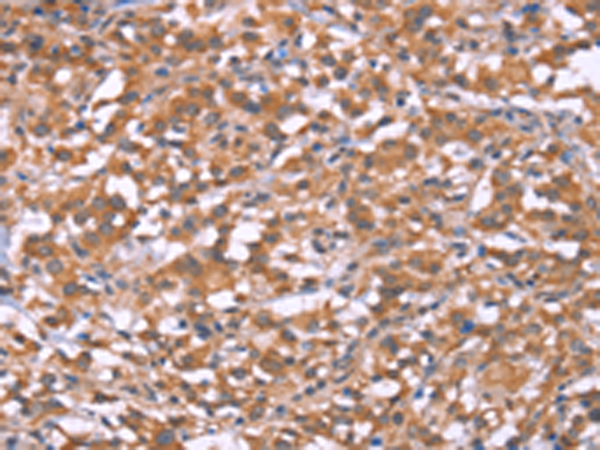

分类: 科研抗体货号: P04845别名: p43; HLD3; EMAP2; SCYE1; EMAPII应用: WB,IHC反应种属: Human, Mouse